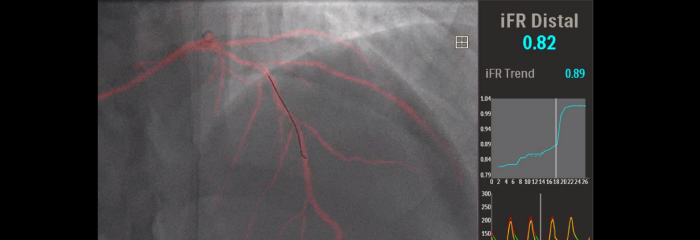

As more CAD patients are considered for minimally invasive interventional therapy, optimal treatment planning is hindered by the fact that 2D coronary angiography has limitations for detecting and assessing coronary stenosis. Data is not consistently and meaningfully connected pre- and intra-procedure, which adds time and complexity to treatment planning. We’ve designed our cardiology solutions to overcome these challenges so you can realise the benefits of clinical efficiency in the cath lab:

Image-guided therapy, iFR, IVUS and haemodynamic monitoring, as well as cardiac pre-procedure planning and advanced applications, are all connected to the image-guided therapy interface to allow viewing, manipulation and custom configuration on the monitor from a single controller at table side or from the control room.